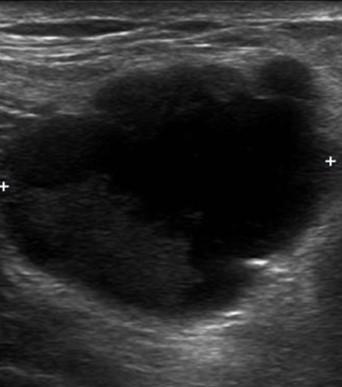

Ung thư vú - Ảnh 2

Ung thư vú

» Thông tin: Nữ giới – 57 tuổi.

» Lâm sàng: Khối tuyến vú.